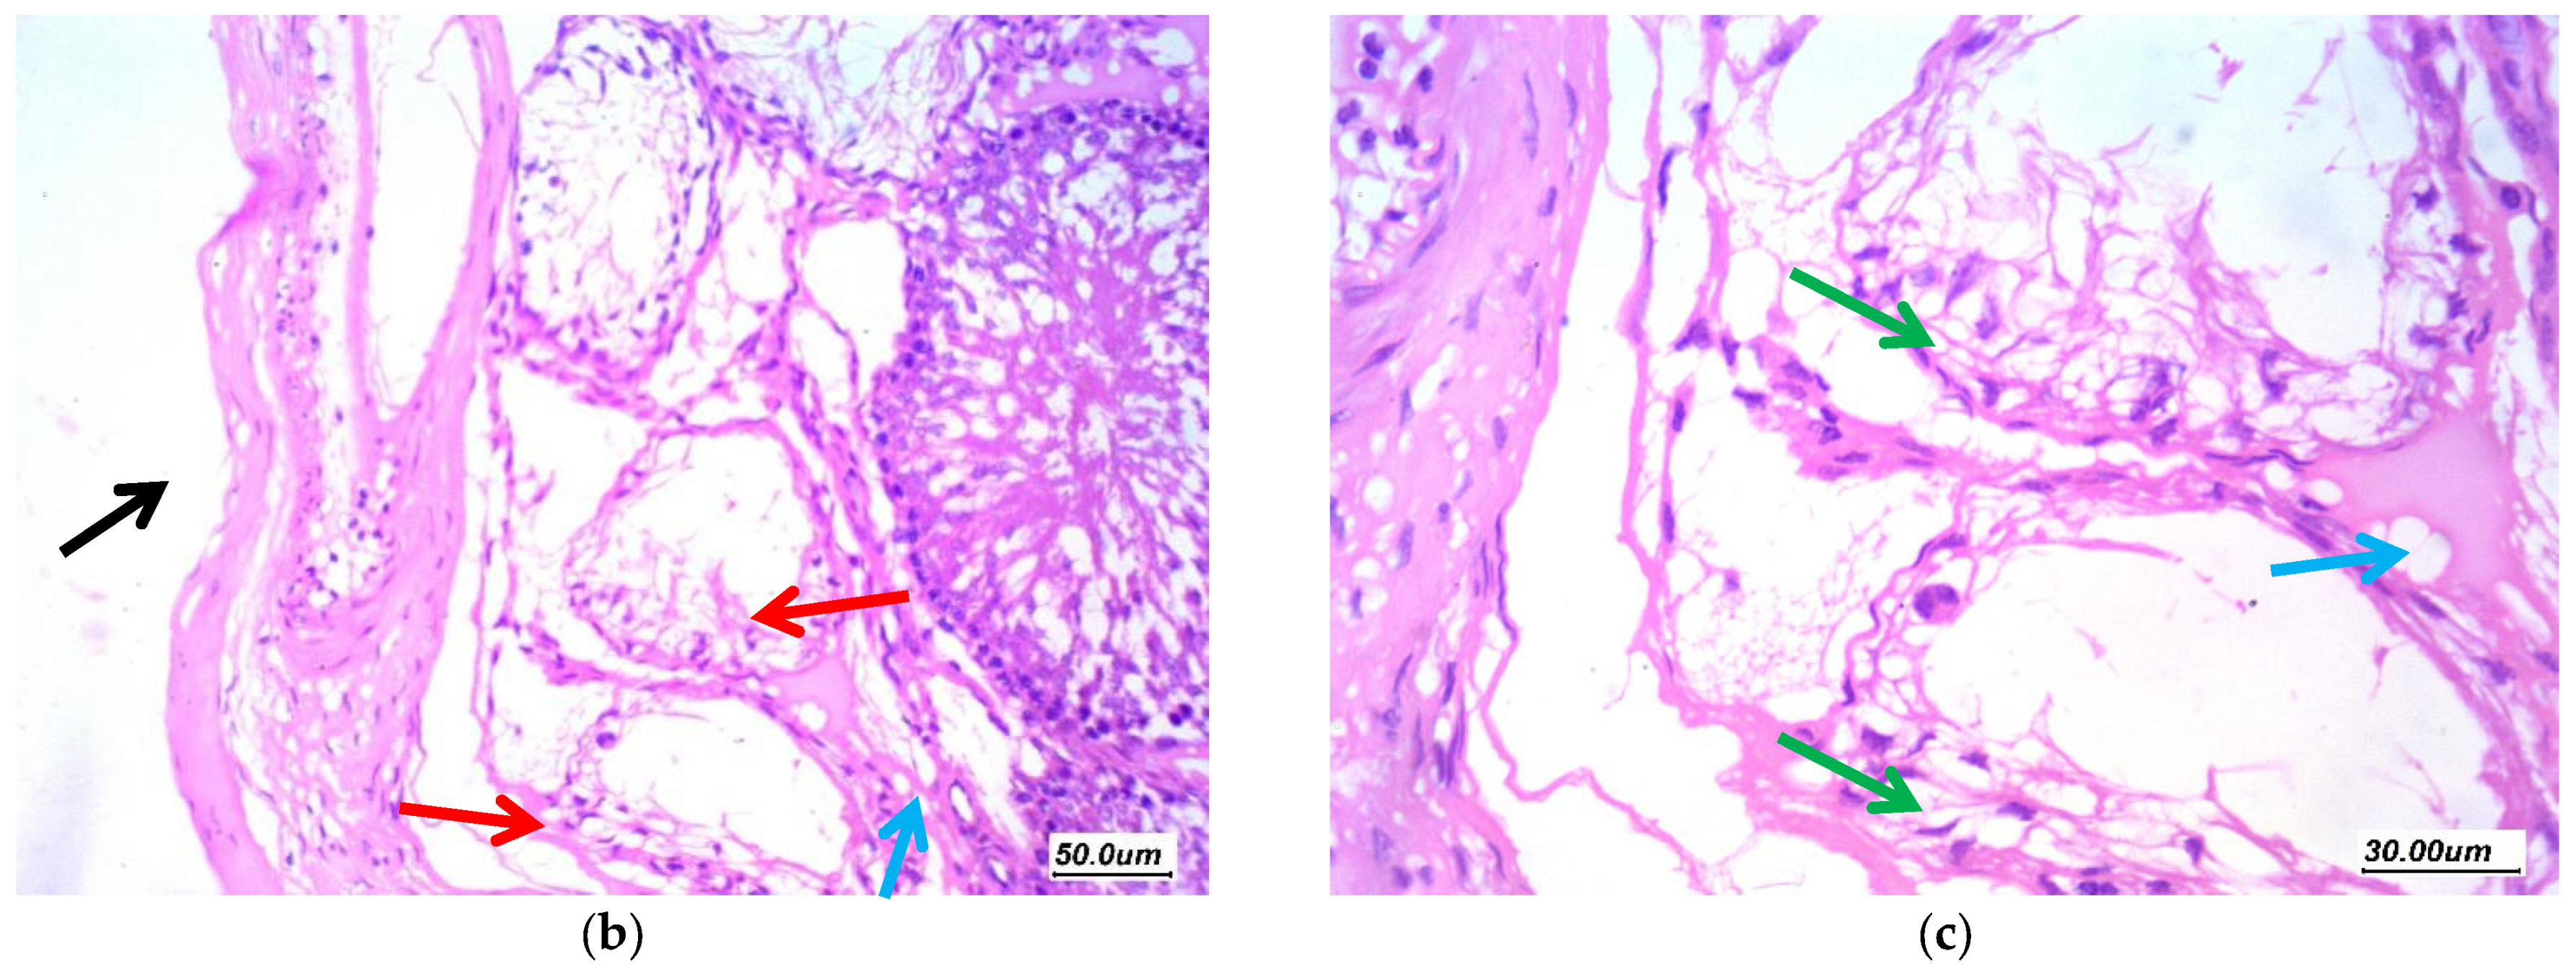

3.7.1. Histopathological Assessment

3.7.2. Morphometric Assessment